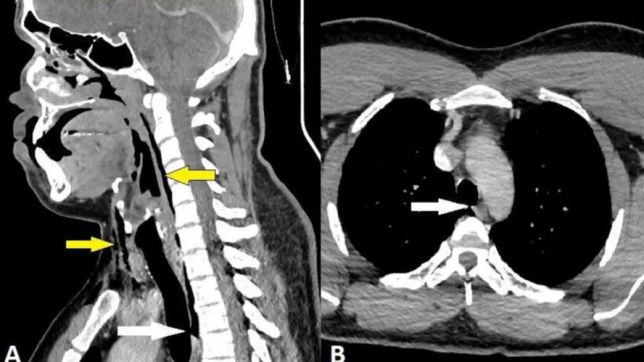

Um exame de tomografia computadorizada de pescoço e tórax revelou uma ruptura na traqueia de 2 mm x 2 mm x 5 mm com pneumomediastino (presença de ar no espaço existente entre os dois pulmões). Ele foi tratado com analgésicos para a dor e antialérgicos para a rinite.

Cinco semanas depois, uma nova tomografia computadorizada revelou a resolução do problema, sem a ruptura na traqueia ou qualquer outra anormalidade.